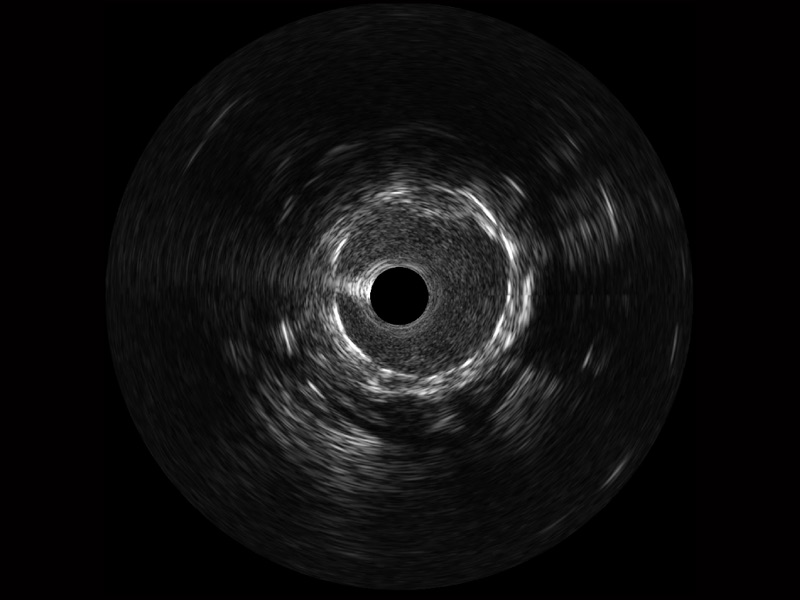

传统IVUS图像

对比传统IVUS导管成像,竞技宝(JJB)官方网站宽频IVUS图像的近场支架梁显影更细腻,远场中膜外血管仍清晰可辨,兼顾远中近,兼顾分辨力与穿透深度